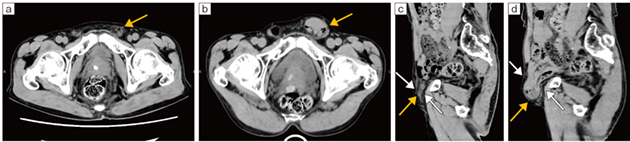

70歳代、男性、鼠径ヘルニアの症例

同日に施行した通常の臥位CT横断像(a)、立位CT横断像(b)、通常の臥位CT矢状断像(c)、立位CT矢状断像(d)を示す。

通常の臥位CT(a、c)では、左鼠径ヘルニアは指摘困難である(←)。またヘルニア門も小さい(c↓)。一方、立位CT(b、d)では、臥位に比べてヘルニア門が大きくなり(d↓)、左鼠径ヘルニアがあって小腸が脱出していることが診断可能となる(←)。この患者は、日常生活、特に立位での左下腹部不快感・左下腹部痛を訴えていたが、通常の臥位CT(a、c)では有症状の状態をとらえられずに診断が困難であることに注意が必要である。